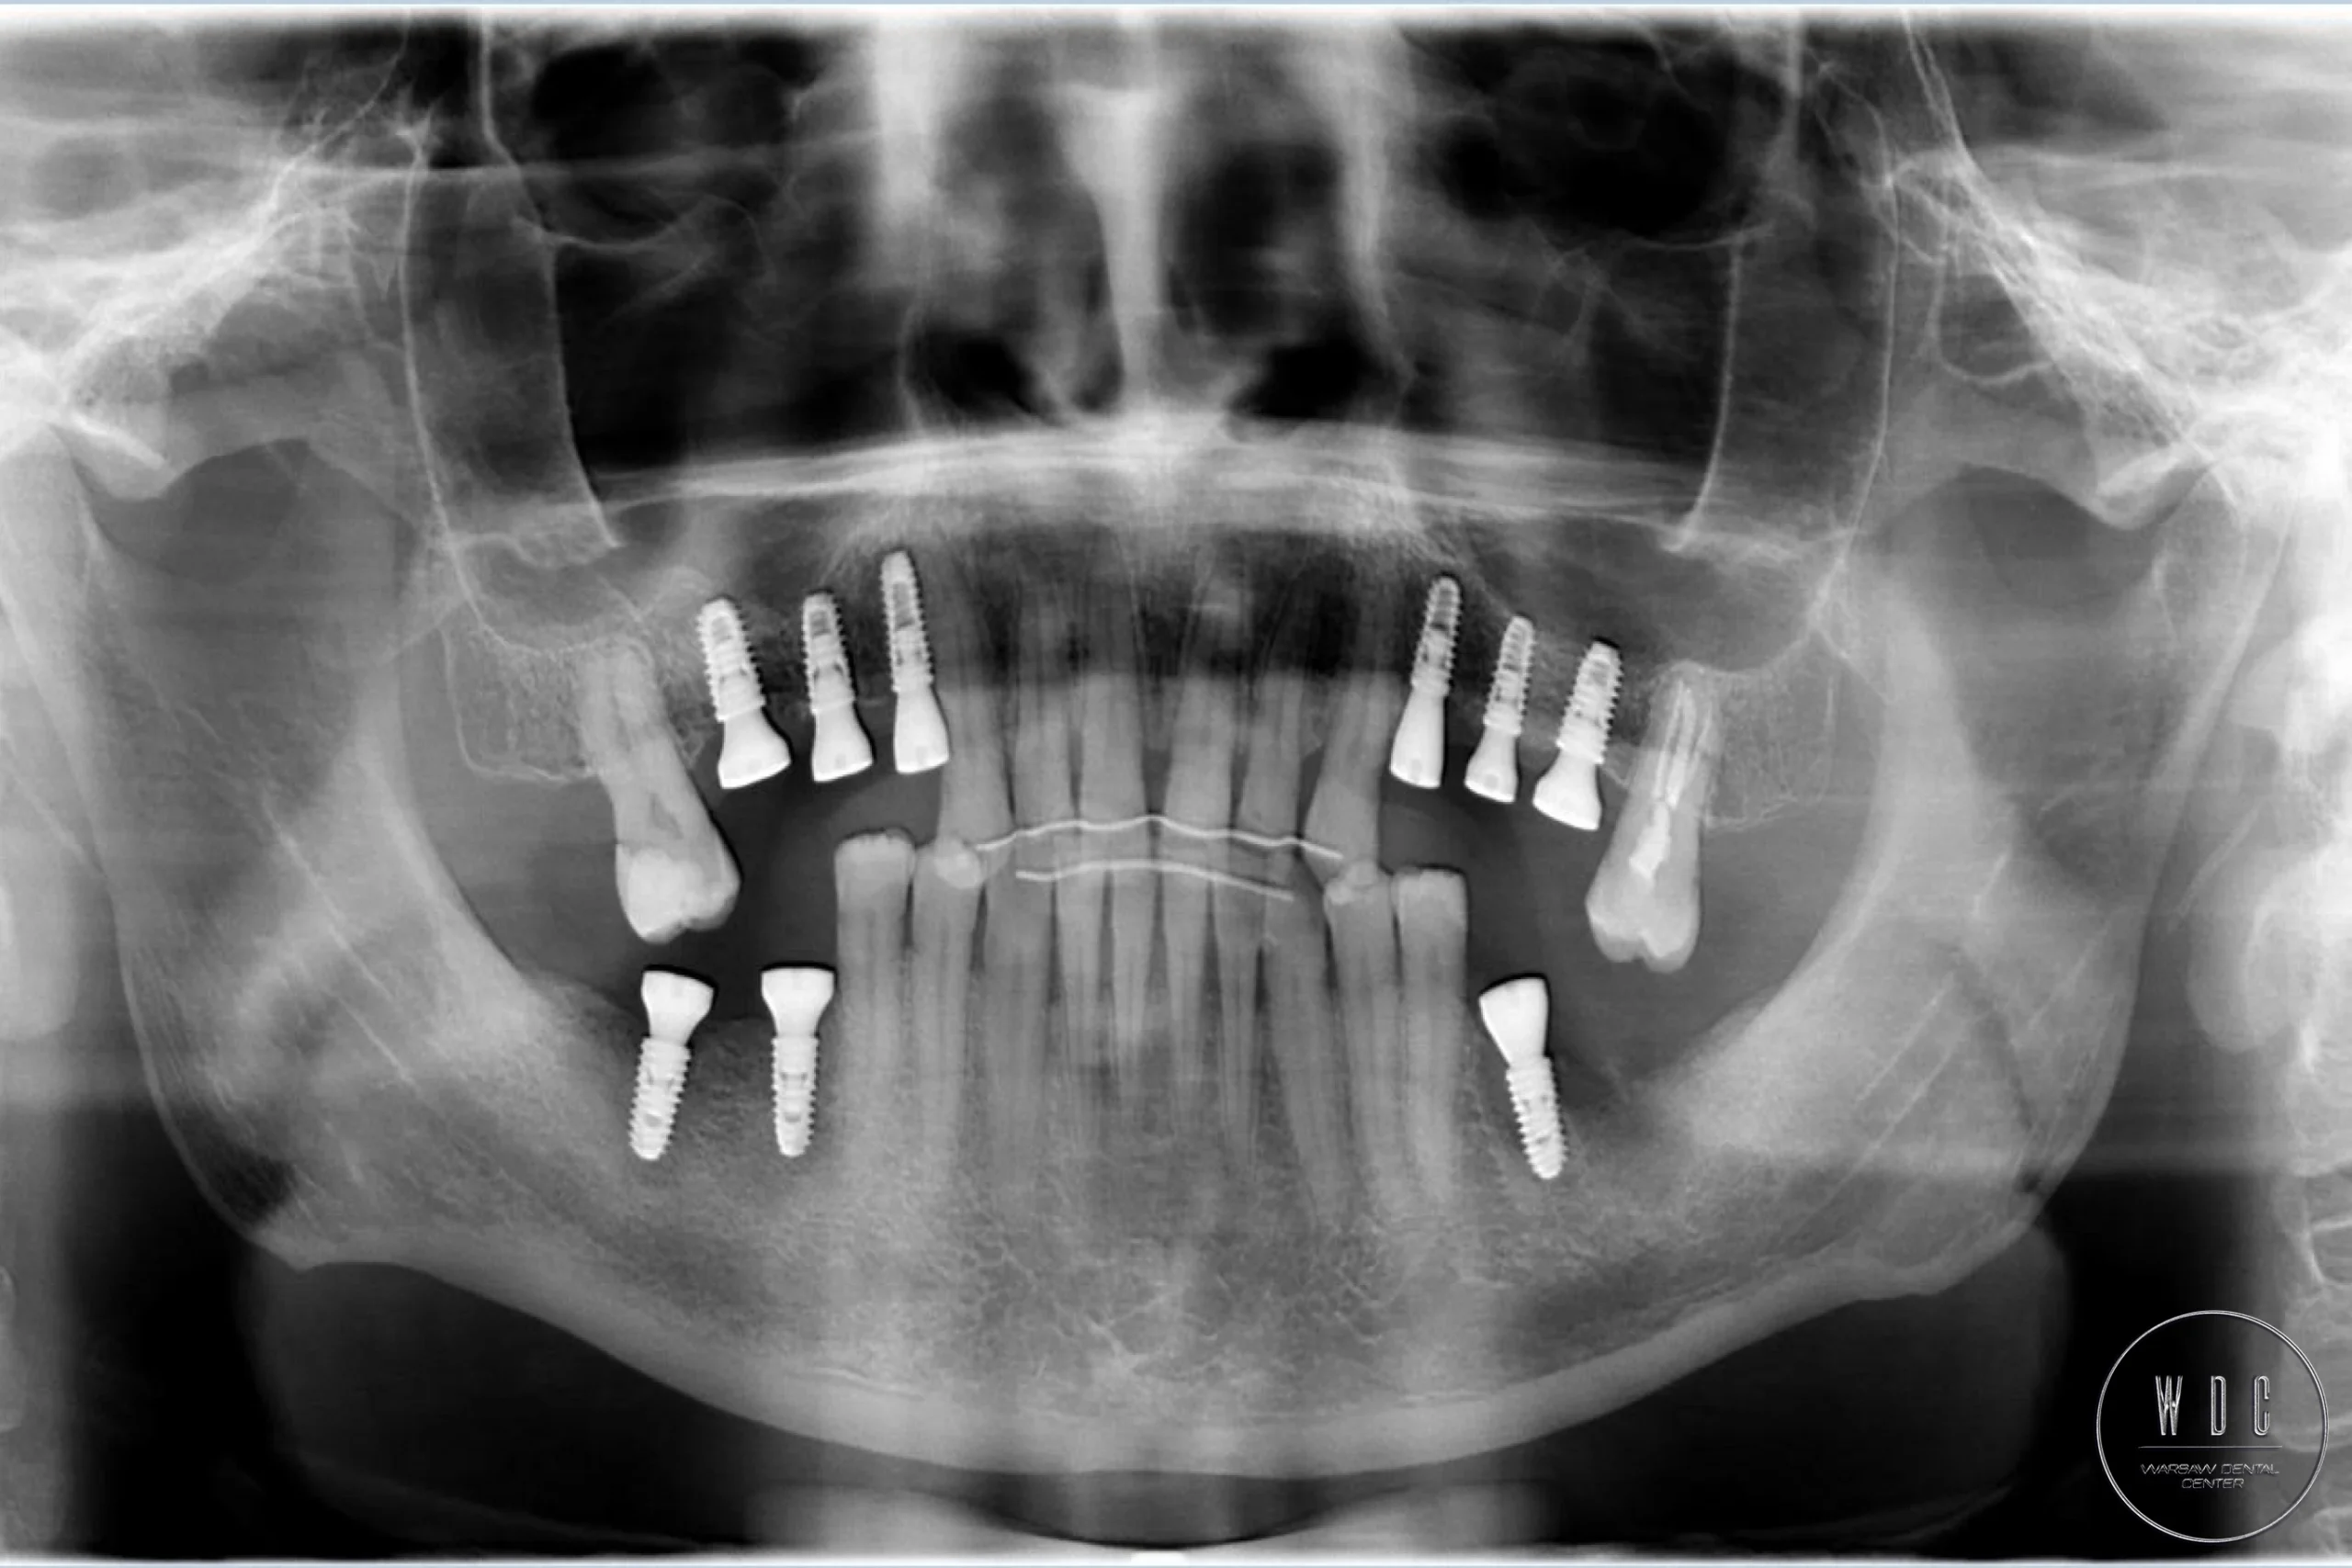

Porozmawiaj z nami o rekonstrukcji zębów na implantach.Nasza nowoczesna technologia wszczepiania implantów dentystycznych oparta na wykorzystaniu szablonów chirurgicznych zapewnia bardziej komfortowe doświadczenie, lepsze wyniki i wyższy wskaźnik sukcesu zabiegu.

Technika ta to specjalistyczne podejście, które wymaga drobiazgowego planowania i wykorzystania zaawansowanego obrazowania 3D do precyzyjnego umiejscowienia implantów dentystycznych. Gwarantuje to ich idealne umieszczenie, znacznie redukuje dyskomfort i przyspiesza czas rekonwalescencji. Kolejnym etapem po wszczepieniu implantu jest założenie śruby gojącej a, po określonym przez chirurga czasie, umieszczenie korony na implancie.

Krok 2: Diagnostyka Badania, takie jak rentgen czy tomografia komputerowa służą ocenie kości szczęki i planowaniu wprowadzenia implantu dentystycznego.

Krok 4: Wszczepienie Implantu zęba Chirurgiczne umieszczenie implantu w kości szczęki w znieczuleniu miejscowym.

Krok 5: Osteointegracja Okres gojenia, podczas którego implant zęba zrasta się z kością.